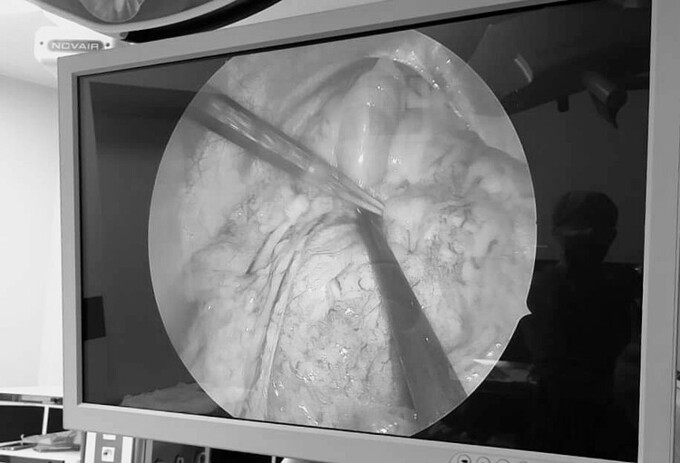

Bệnh nhi ngay sau đó được chỉ định phẫu thuật nội soi khoang màng phổi trái, đẩy tạng thoát vị về đúng vị trí, khâu phục hồi khuyết tật cơ hoành trái.